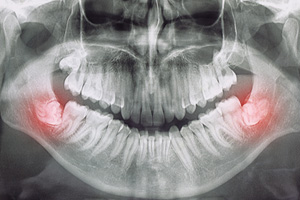

Most people have all four wisdom teeth, but some people have three, two, one, or none. Research suggests that between 5% and 37% of people are missing one or more wisdom teeth, and it is quite likely that genetic factors play a large role in determining how many third molars a person will have. However, you may still have wisdom teeth even if you can’t see them since it’s possible for these third molars to remain submerged in the gum tissue if they fail to erupt properly. The only way to determine precisely how many wisdom teeth you have is to have a dental X-ray at our office in Hackensack. Most people’s wisdom teeth will begin to emerge between the ages of seventeen and twenty-one, but some receive them sooner or later than that.